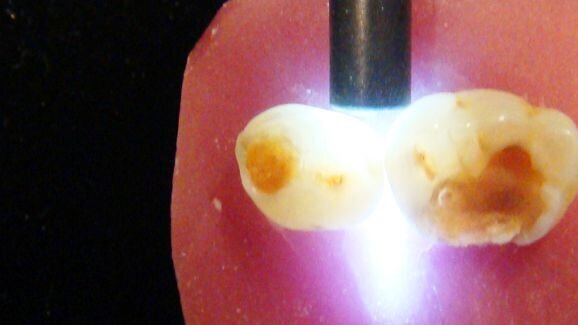

The sensitivity of a detection method relates to its ability to detect the disease when it is present, and the specificity relates to the ability to detect the absence of the disease when it is not present. Occlusal caries detection is complicated clinically by surface morphology, past fluoride exposure, anatomical fissure topography, and the presence of plaque and stains. Commonly used methods for this type are visual and tactile inspection, radiography, transillumination and laser fluorescence. This method, namely DIAGNOdent (KaVo), is promoted for use for both occlusal and interproximal lesion detection, with the technology based on the fluorescence of porphyrins excited by laser light at a wavelength of 655 nm. The sensitivity and specificity of laser fluorescence in detecting intra-dentinal lesions varies greatly, with false positives, the major limiting factor of the technology. In order to achieve the best results, the angulation of the tip should be consistent, and the results should be seen in conjunction with other detection methods, not as a stand-alone gold standard.

Recently developed quantitative light-induced fluorescence systems (including QLF, Inspektor Research Systems, and SOPROLIFE, ACTEON) utilise differences in auto-fluorescence between sound and demineralised enamel and dentine. Demineralised enamel appears darker than the adjacent sound tooth structure, and the carious dentine fluoresces red depending on the filters used. The use of QLF (wavelength 405 nm) enables the early detection of enamel demineralisation, and it may be used to discriminate between affected and infected dentine. Like DIAGNOdent, QLF technology is reliant on standardised techniques, especially control of ambient light, and the results must be seen in conjunction with other methods. SOPROLIFE uses a longer wavelength of 450 nm, and has settings for the diagnosis of carious dentine, as well as a treatment mode, which assists in determining which dentine should be removed.

The method of fibre-optic transillumination is based on the principle that sound tooth structure has a higher index of light transmission than a carious tooth does. Units such as the SDI diagnostic tip for SDI’s light curing unit or the NSK transillumination handpiece are simple to use. The light source is placed on the buccal or lingual side of the tooth. Transillumination is primarily used for the detection of proximal carious lesions, although studies have indicated it can also improve visual detection of occlusal lesions. Carious lesions limited to the enamel appear as grey shadows, and those in the dentine appear as orange-brown or bluish shadows.